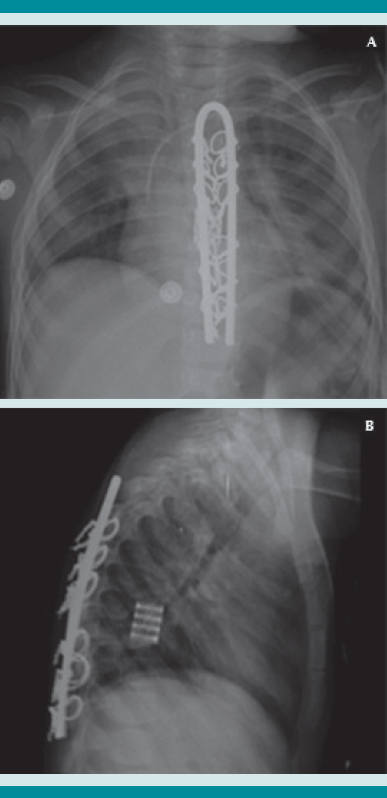

En la sesión multidisciplinaria hospitalaria se decidió que la mejor opción sería el tratamiento quirúrgico radical, que incluyó: toracotomía anterior, corporectomía (T7-T8), resección y toma de cultivo de granuloma (Figura 8), aplicación de una malla de titanio con injerto autólogo y matriz ósea (Figura 9), instrumentación posterior con barra de Luque y alambrado sublaminar de T4 a T11 (Figura 10 a-b), que se llevó a cabo sin complicaciones transoperatorias, posoperatorias inmediatas ni mediatas.

A manera de protección se utilizó un corsé de Jewett a permanencia. La evolución a los cuatro meses de la instrumentación por doble acceso fue satisfactoria. El paciente se encuentra actualmente con marcha independiente, bipodálica, no claudicante y neurológicamente íntegro. Se iniciaron las sesiones de rehabilitación con restricción absoluta de actividades de contacto o alto impacto.